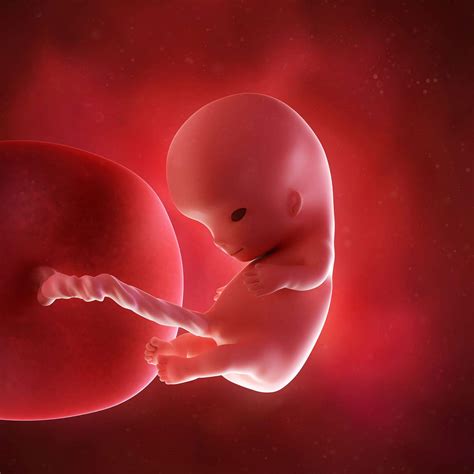

A 10 week fetus ultrasound is a medical imaging technique used to visualize the fetus inside the uterus. At this stage, the fetus is about the size of a small strawberry, measuring approximately 3.1 cm (1.2 inches) in length from crown to rump. The ultrasound provides valuable information about the fetus's development, including the heartbeat, size, and overall health.

• Organ Development: At this stage, the fetus's major organs, such as the heart, brain, and kidneys, are beginning to form.

At 10 weeks, the fetus is rapidly developing, and the ultrasound can reveal several important details:

• Fetal Movement: Although it's too early for the mother to feel, the fetus may exhibit slight movements, such as curling and uncurling.